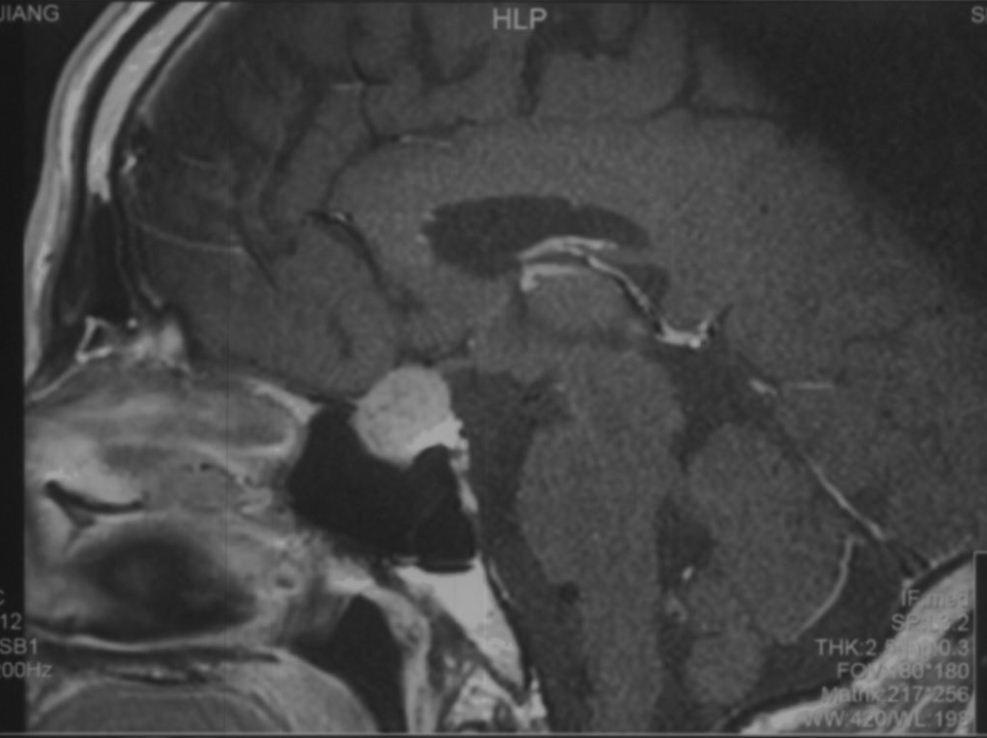

患者为中年患者,因头痛伴视物模糊半年起来就诊,鞍区增强MRI示:鞍区占位性病变,肿瘤大小约2.5cm,肿瘤突破鞍隔向上生长,顶部偏向右侧,视交叉受压明显,两侧侵犯海绵窦。T1WI为等信号,T2WI为混杂等信号,明显强化。复旦大学附属肿瘤医院神经外科高阳

术前磁共振图像: